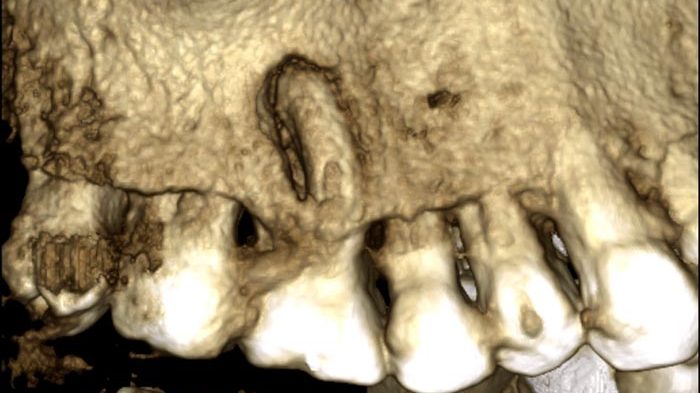

Caso clínico en el que por la anatomía del diente y la complicación del diagnóstico se requiere instrumentación…